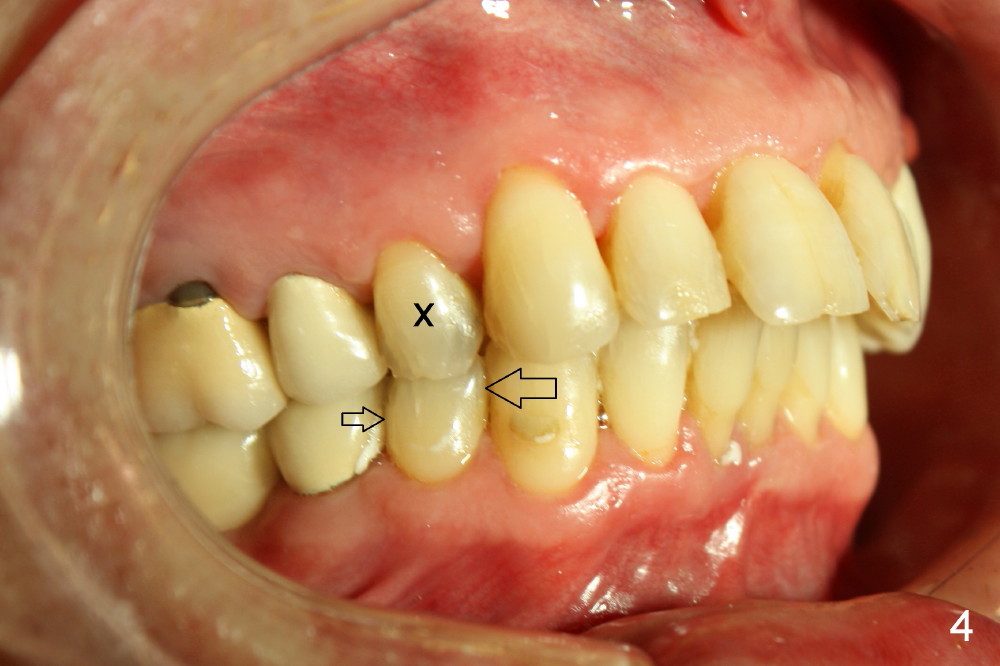

A 66-year-old man has dreamed to correct his bite since childhood. The malocclusion is characterized by deviation of the upper midline to the left (Fig.2), Class II occlusion on the right (Fig.1), and Class I occlusion on the left (Fig.3).

Although there is apical infection associated with the upper left first bicuspid (Fig.3 *), orthodontic treatment consists of extraction of a single tooth: the upper right first bicuspid (Fig.4,5: x), minor movement of the posterior teeth (Fig.4,5 smaller arrow) and major movement of the anterior teeth (bigger arrow). Fig.6 shows simulated tooth movement.